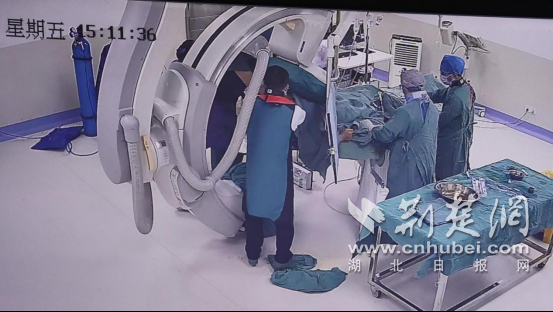

- 十堰市中西医结合医院胸脑外科团队精准介入治疗成功挽救危重患者生命